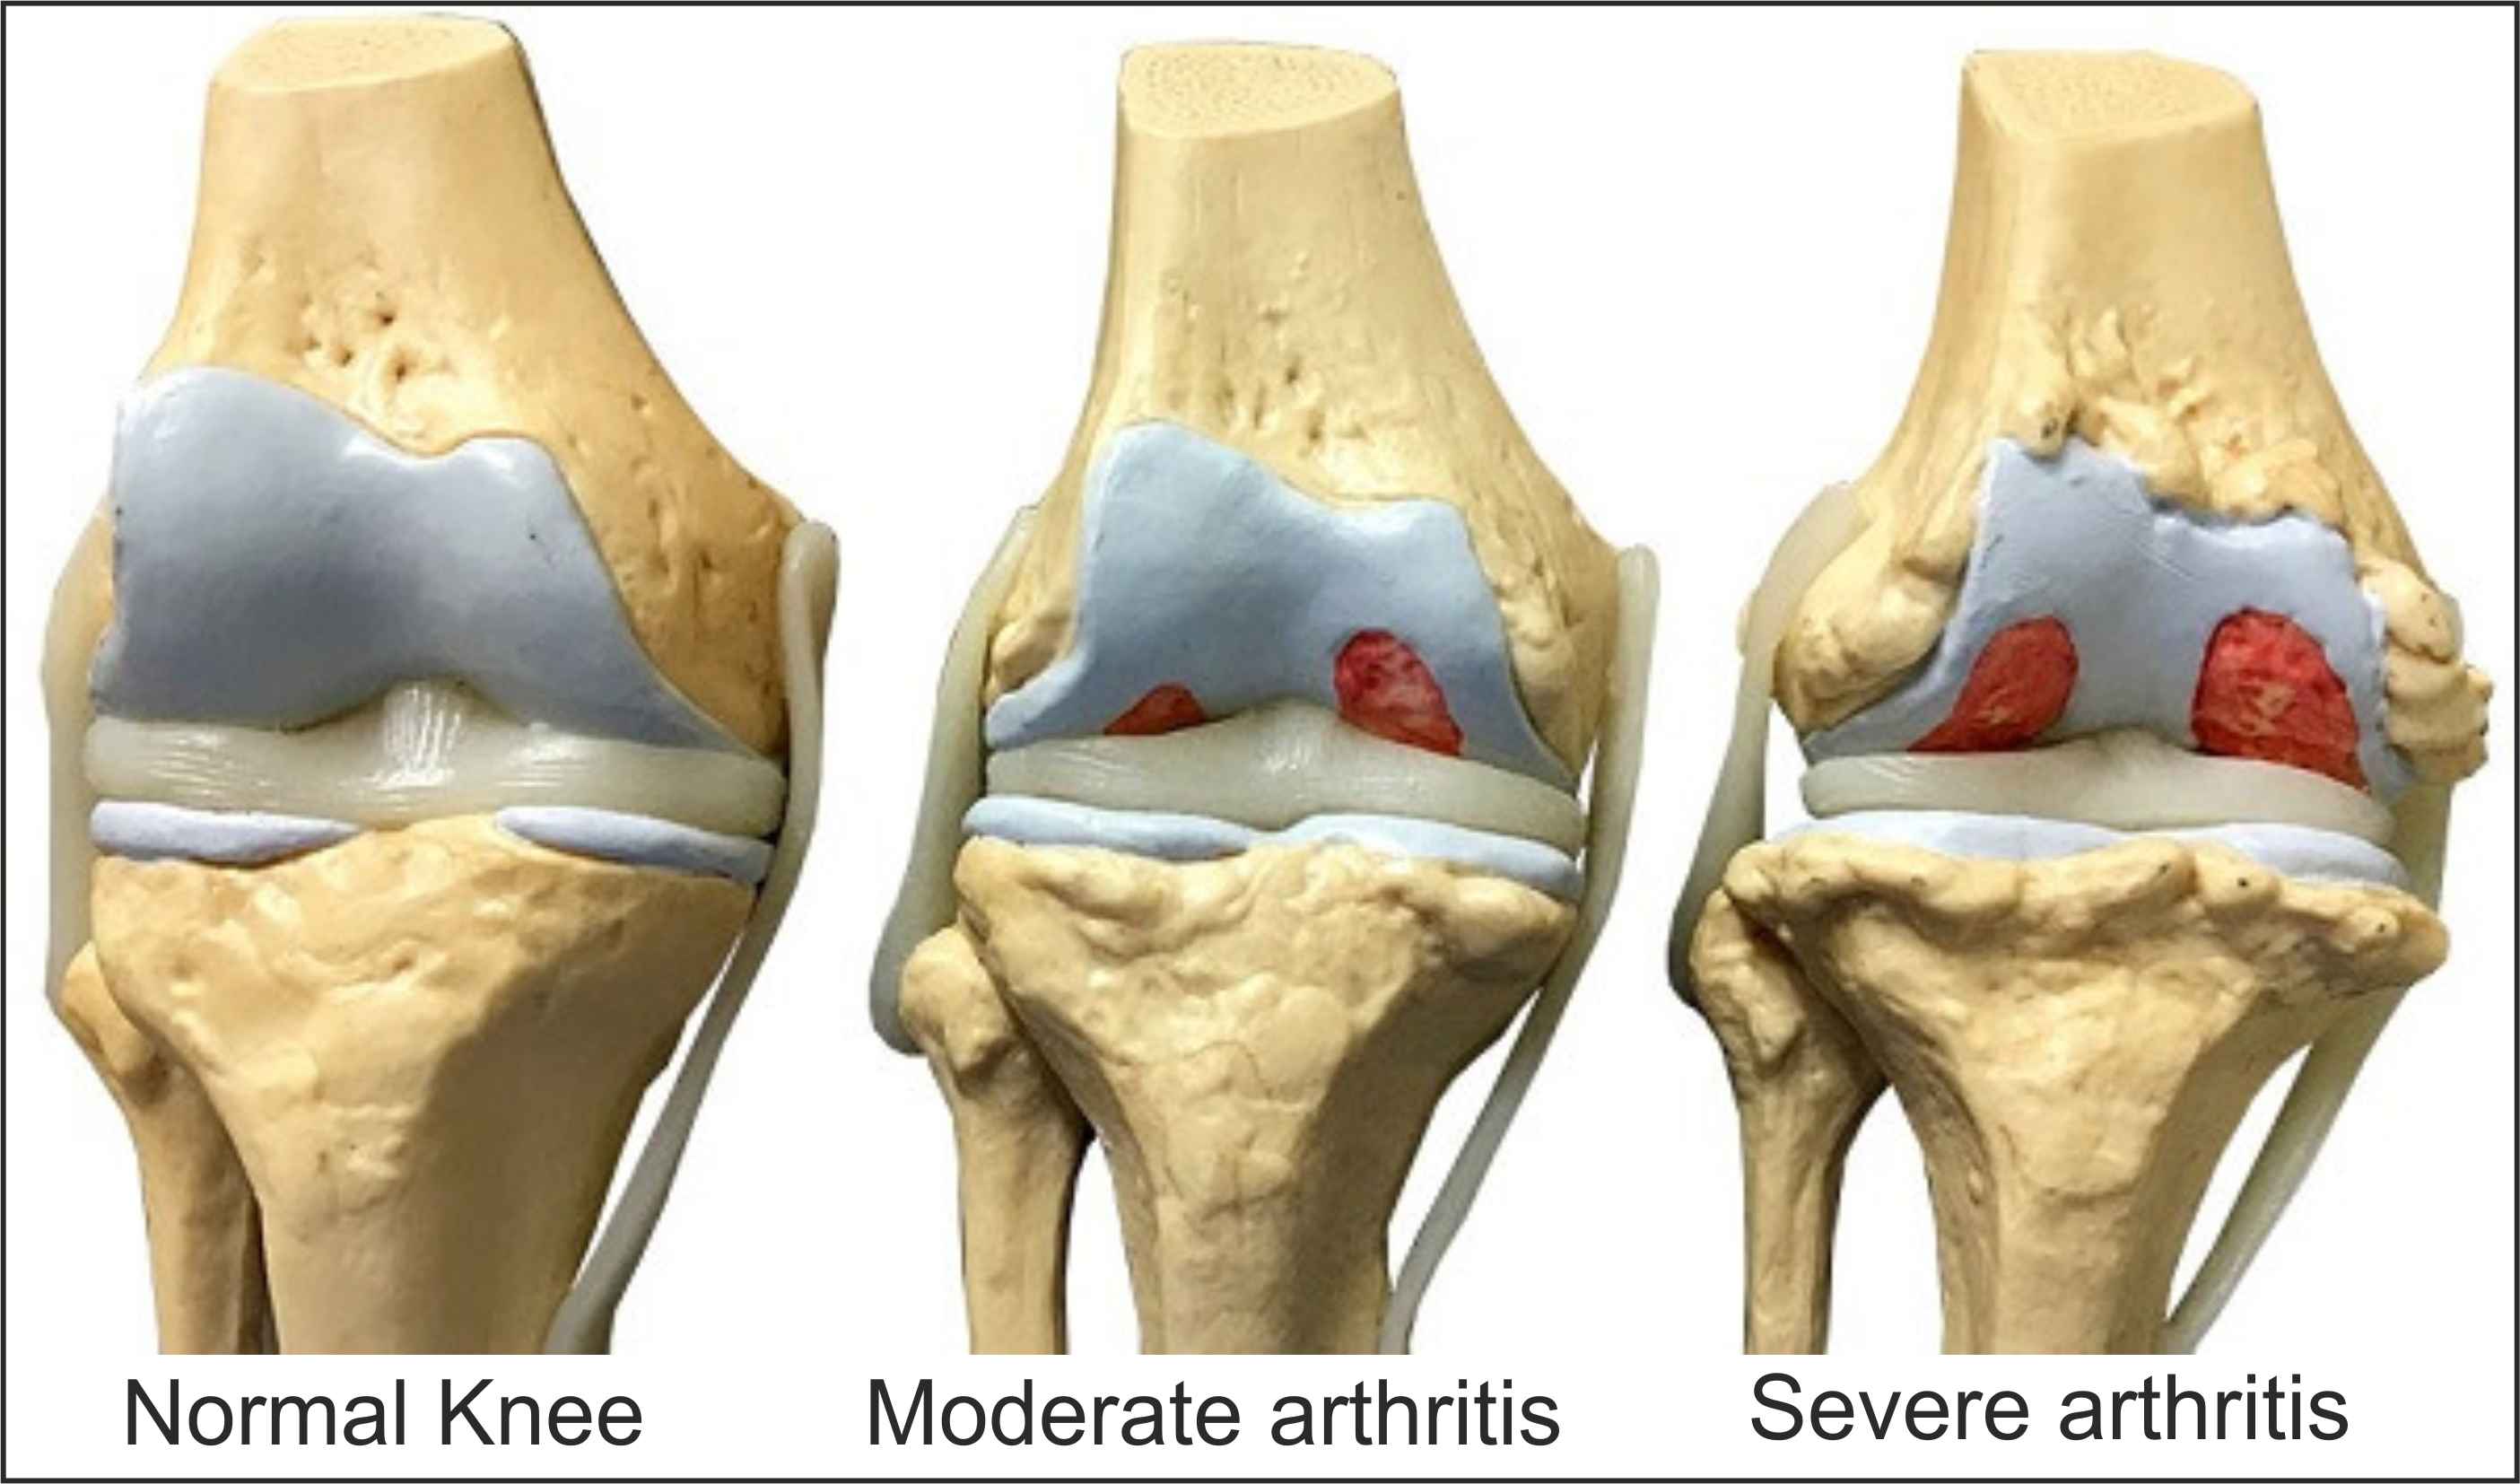

Exact reason is not known. Stress on articular cartilage and bone leads to wear and tear to these structures. Joint inflammation is very minimum compare to other arthritis and seen mostly in advanced disease.

Pain around the joint that increases with weight bearing and movement and improves with rest. It may be associated with morning stiffness and swelling of the joints. Clinical signs are tenderness, crepitus, joint effusion, decreased range of movement,etc. X-ray shows decreased joint space, osteophytes formation and osteoporosis of bone.